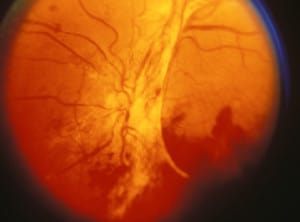

Причината за развитието на това заболяване се корени в това, че диабетът поразява малките кръвоносни съдове, които доставят хранителни вещества до ретината. Вследствие на диабета тези съдове се стесняват, пропускливостта на съдовата стена се повишава, като се блокира и доставянето на хранителни вещества до клетките в ретината. Зрението се замъглява поради изливане на кръв или течност в ретиналната тъкан. Ако кръвта и течността засегнат голяма част от ретината, както и отговорната за централното зрение макула. Когато тя бъде засегната последиците са неясно зрение, като човекът спира да улавя фините детайли. Затруднено е извършването на ежедневни дейсности като шофиране, четене и гледане на телевизия. Получава се оток на макулата, недостатъчен приток на кръв към нея, увеличаване на нови съдове, което води до значителна загуба на зрение или слепота.